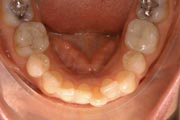

Crowding

After